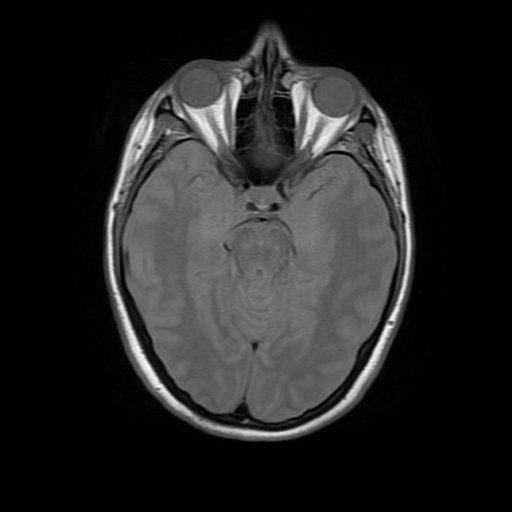

Brain MRI